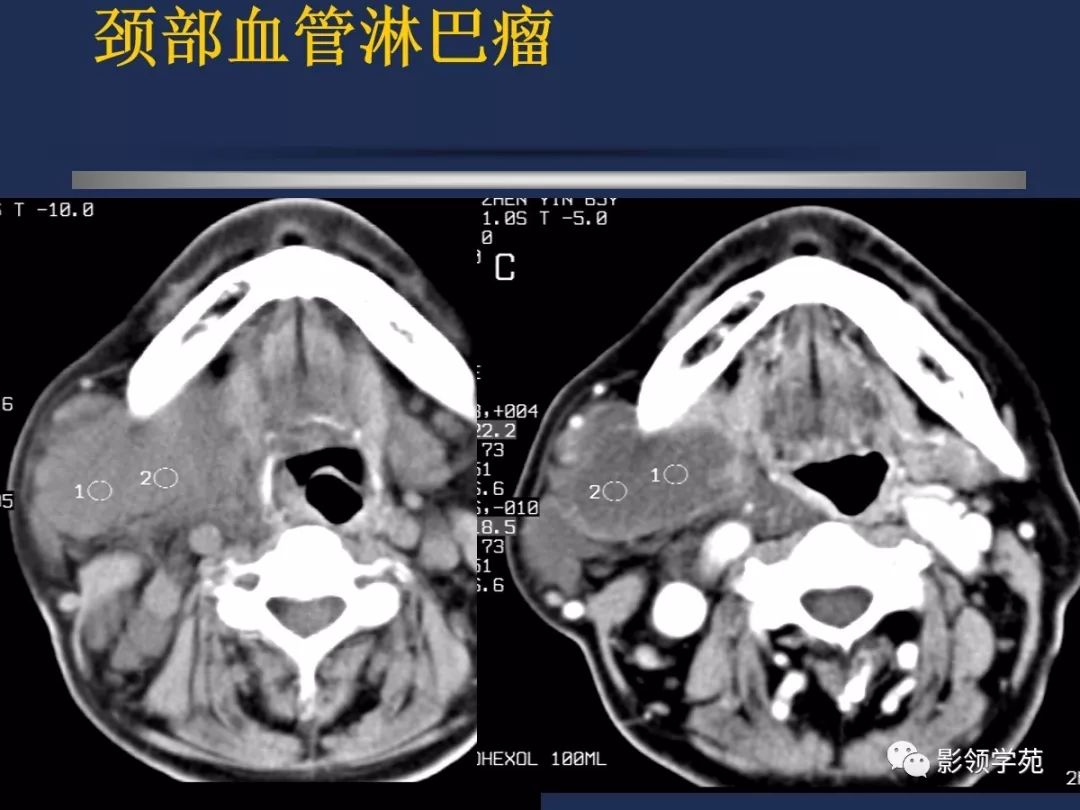

颈部常见疾病影像诊断

- 血管瘤

- 颈动脉体瘤

- 淋巴结肿大性疾病